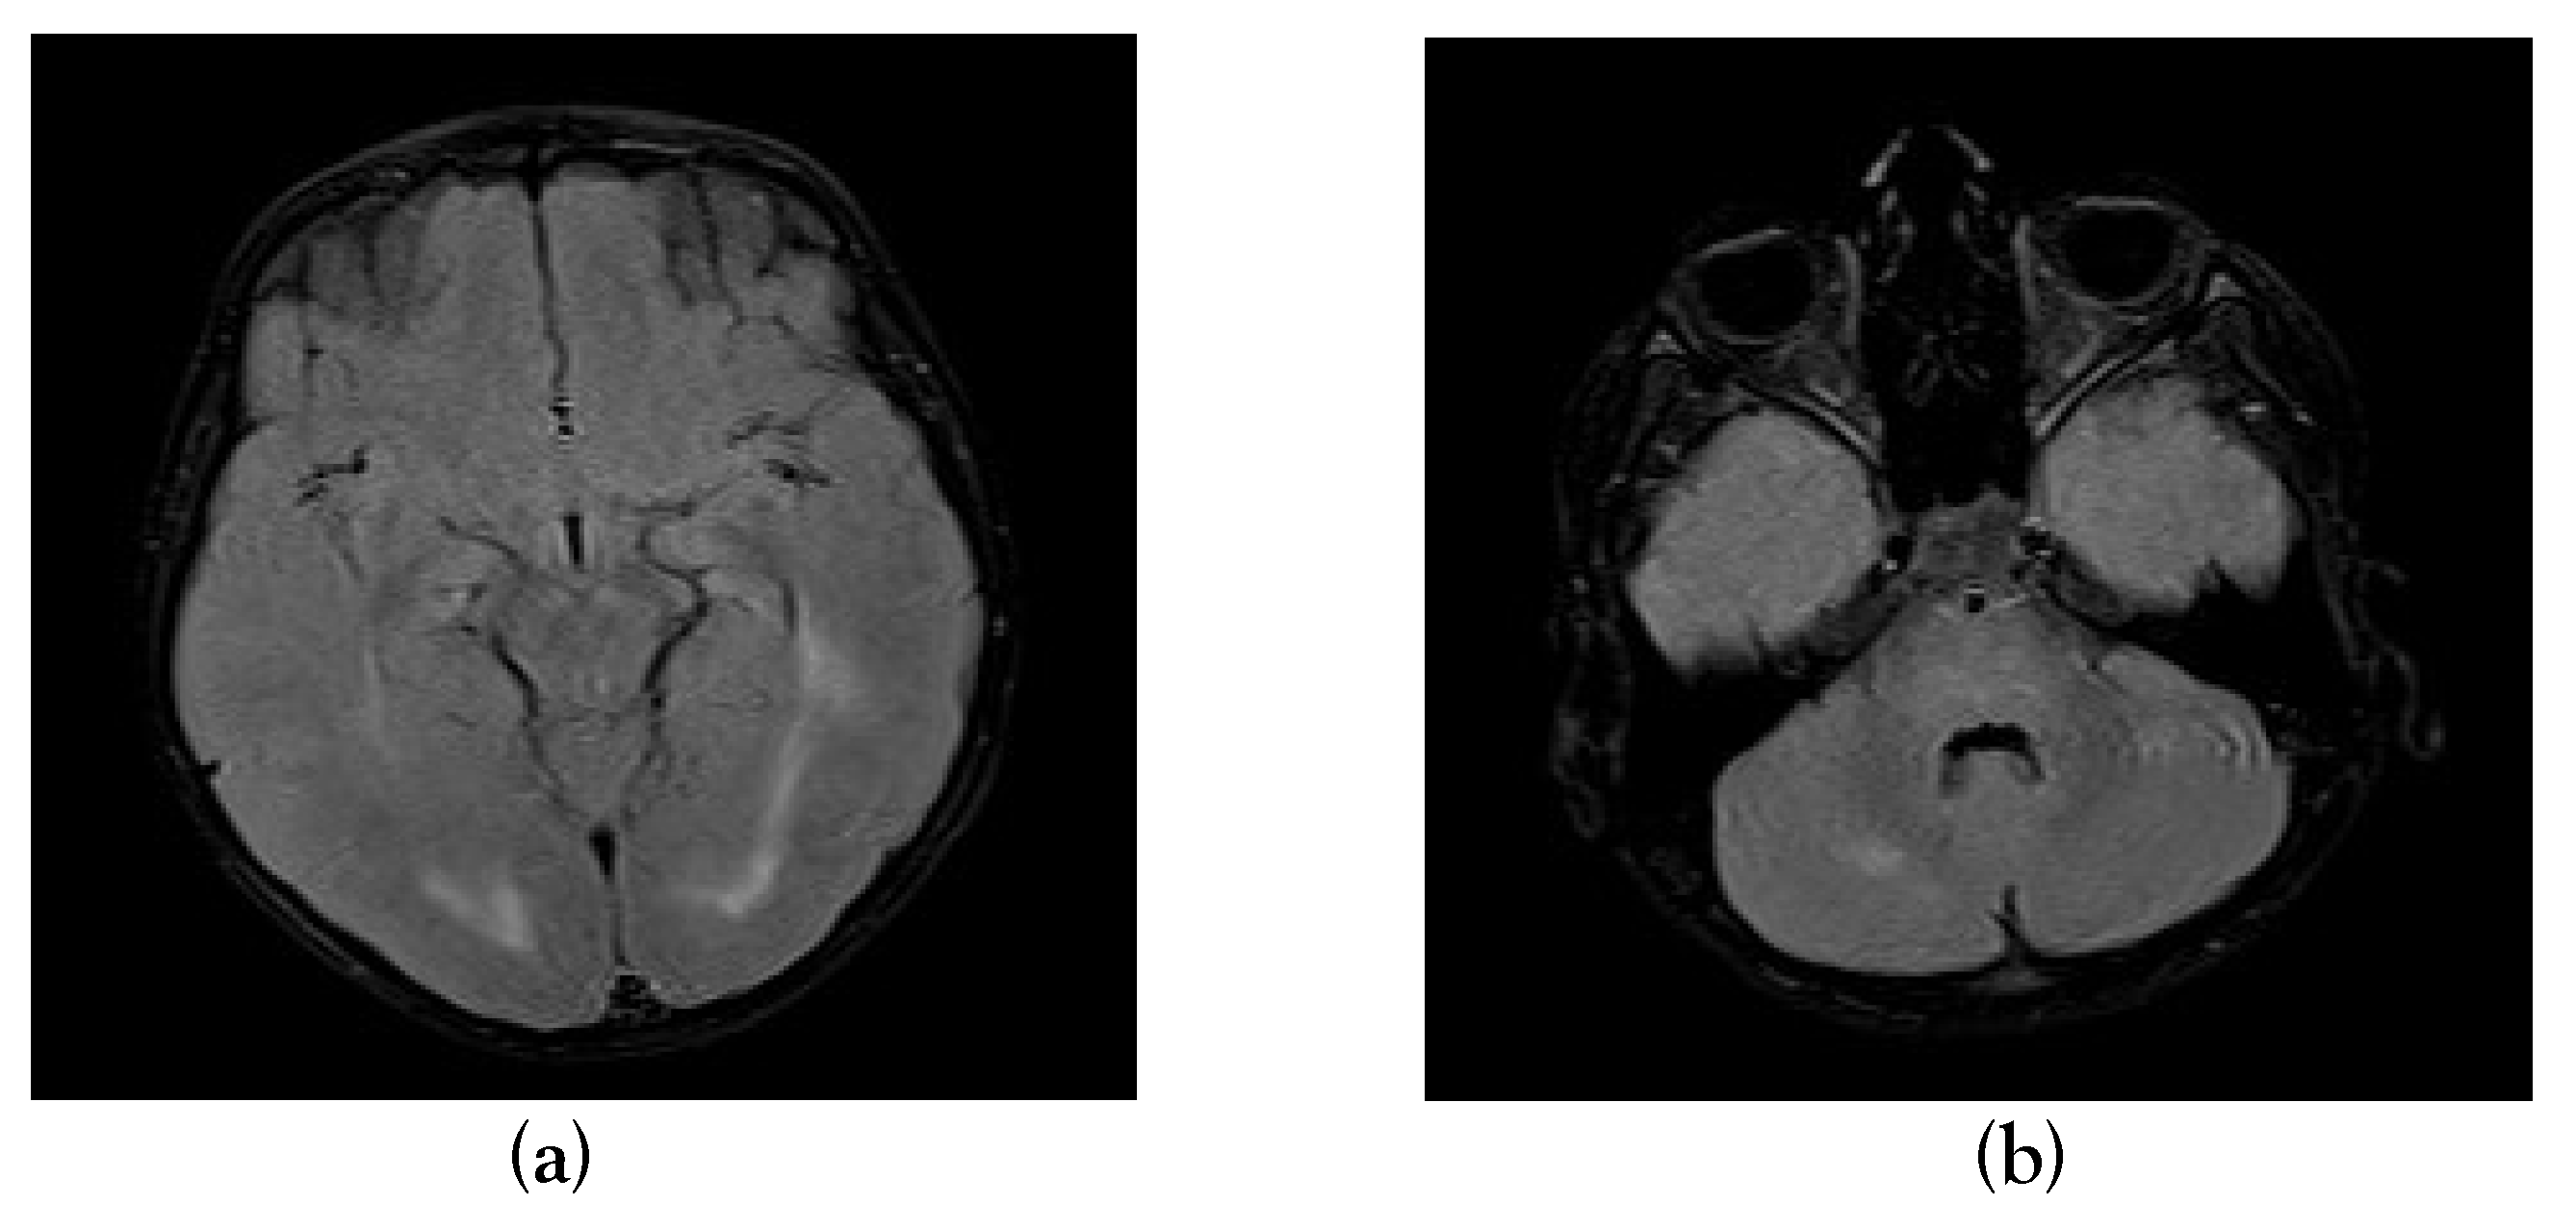

A Case Report of Acute Disseminated Encephalomyelitis Following Severe Dengue in a Child